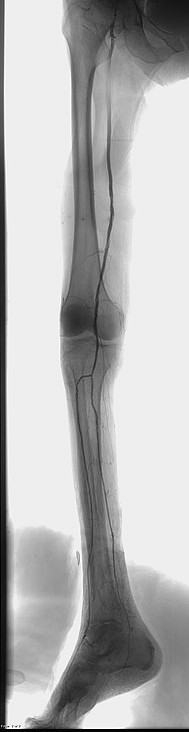

The Zilver Vena Venous Self-Expanding Stent is the world’s first-ever stent designed to specifically treat symptomatic iliofemoral venous outflow obstruction. I used this device in a off label setting for this hemodyalisis patient with rapid recurrent strong subclavian vein restenosis after angioplasty. I hope to take the advantage of this features to solve problem of my patient:

large stent diameter to fit this big vessel (14mm)

consistently strong radial force from end to end

flexibility and kink-resistance